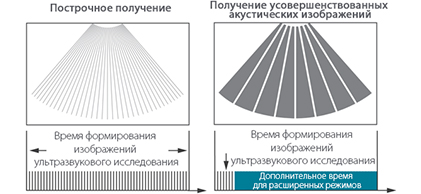

Платформа ZST+

Технология ультразвукового сканера MX7, которая обеспечивает быстрое и точное отображение, уменьшает артефакты движения и обладает более высокой частотой обновления кадров.